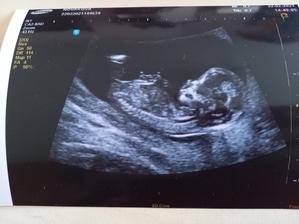

1.2.2021 - kontrola 9+5tt srdíčko bije, plod má 3 cm, termín porodu 1.9.2021 ❤

22.2.2021 - 1. Screening NT - krev nevyšla dobře, ale ultrazvuk vyšel v pořádku, raději jsme posláni na lepší ultrazvuk do nemocnice, zde vše v pořádku, riziko sníženo z 1: 634 na 1: 9324 a vyhodnocen jako negativní

1.3.2021 - kontrola v 13+5 tt vše vypadá v pořádku, pohlavní buňky naznačují kluka